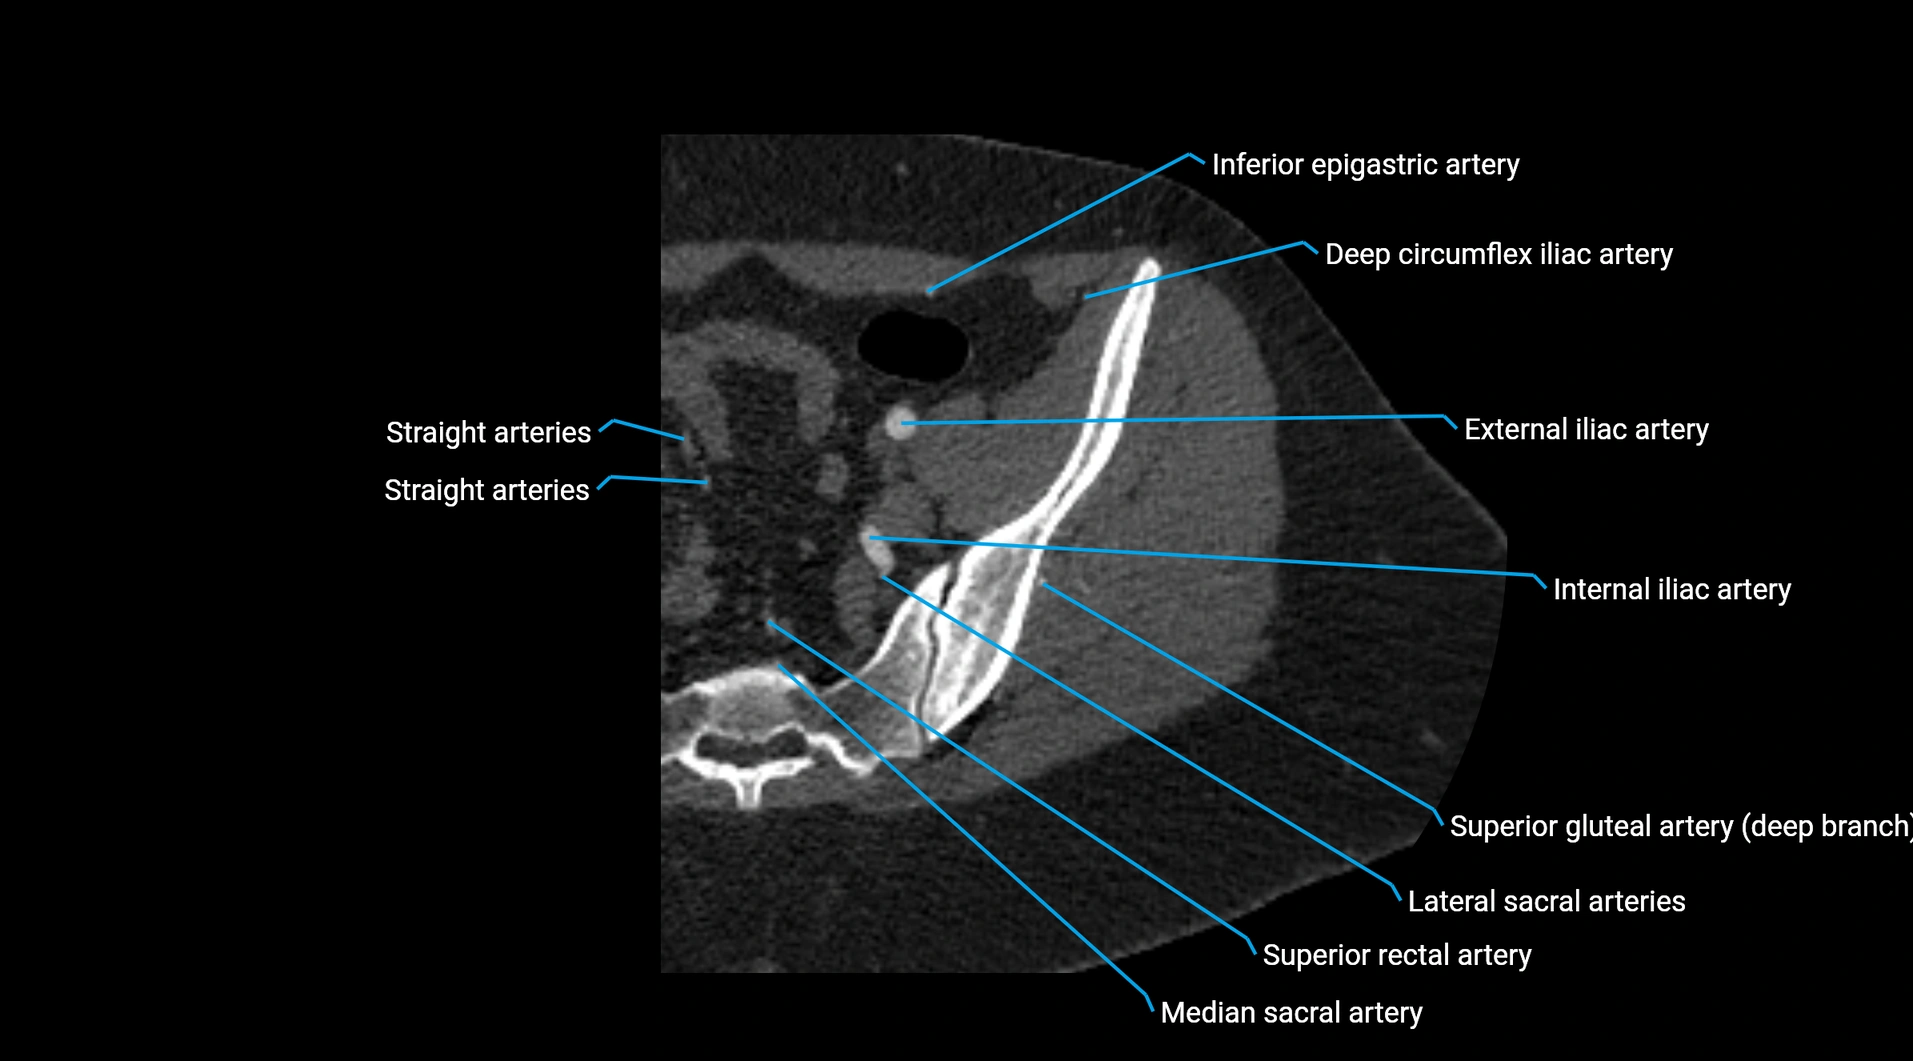

• Parietal branches: inferior phrenic arteries, lumbar arteries, median sacral artery

• Terminal branches: right and left common iliac arteries

Contrast-enhanced CT (CTA):

• Gold standard for abdominal aortic imaging

• Provides excellent detail of lumen, wall, aneurysm, thrombus, and branch vessels

• Multiplanar and 3D reconstructions help in aneurysm measurement, stent graft planning, and dissection evaluation

• Detects acute rupture, traumatic injury, or occlusion with high sensitivity